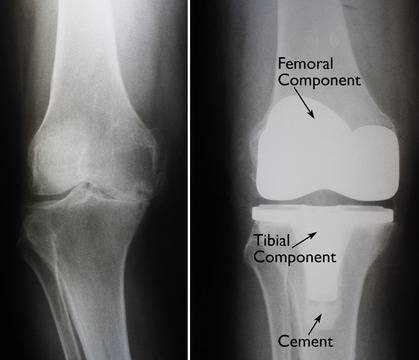

Ендопротезиране на колянна става Ендопротезирането на колянна става е една от най-честите и най-успешни ортопедични операции. След извършването на ендопротезиране на увредената става с изкуствена става. Най- често титаниева, болката изчезва, движенията се възстановяват и пациентите се завръщат към нормалните дейности от ежедневието. При тотално ендопротезиране се извършва заместване на цялата става. Както бедрената компонента, така и Read more about Ендопротезиране на колянна става[…]